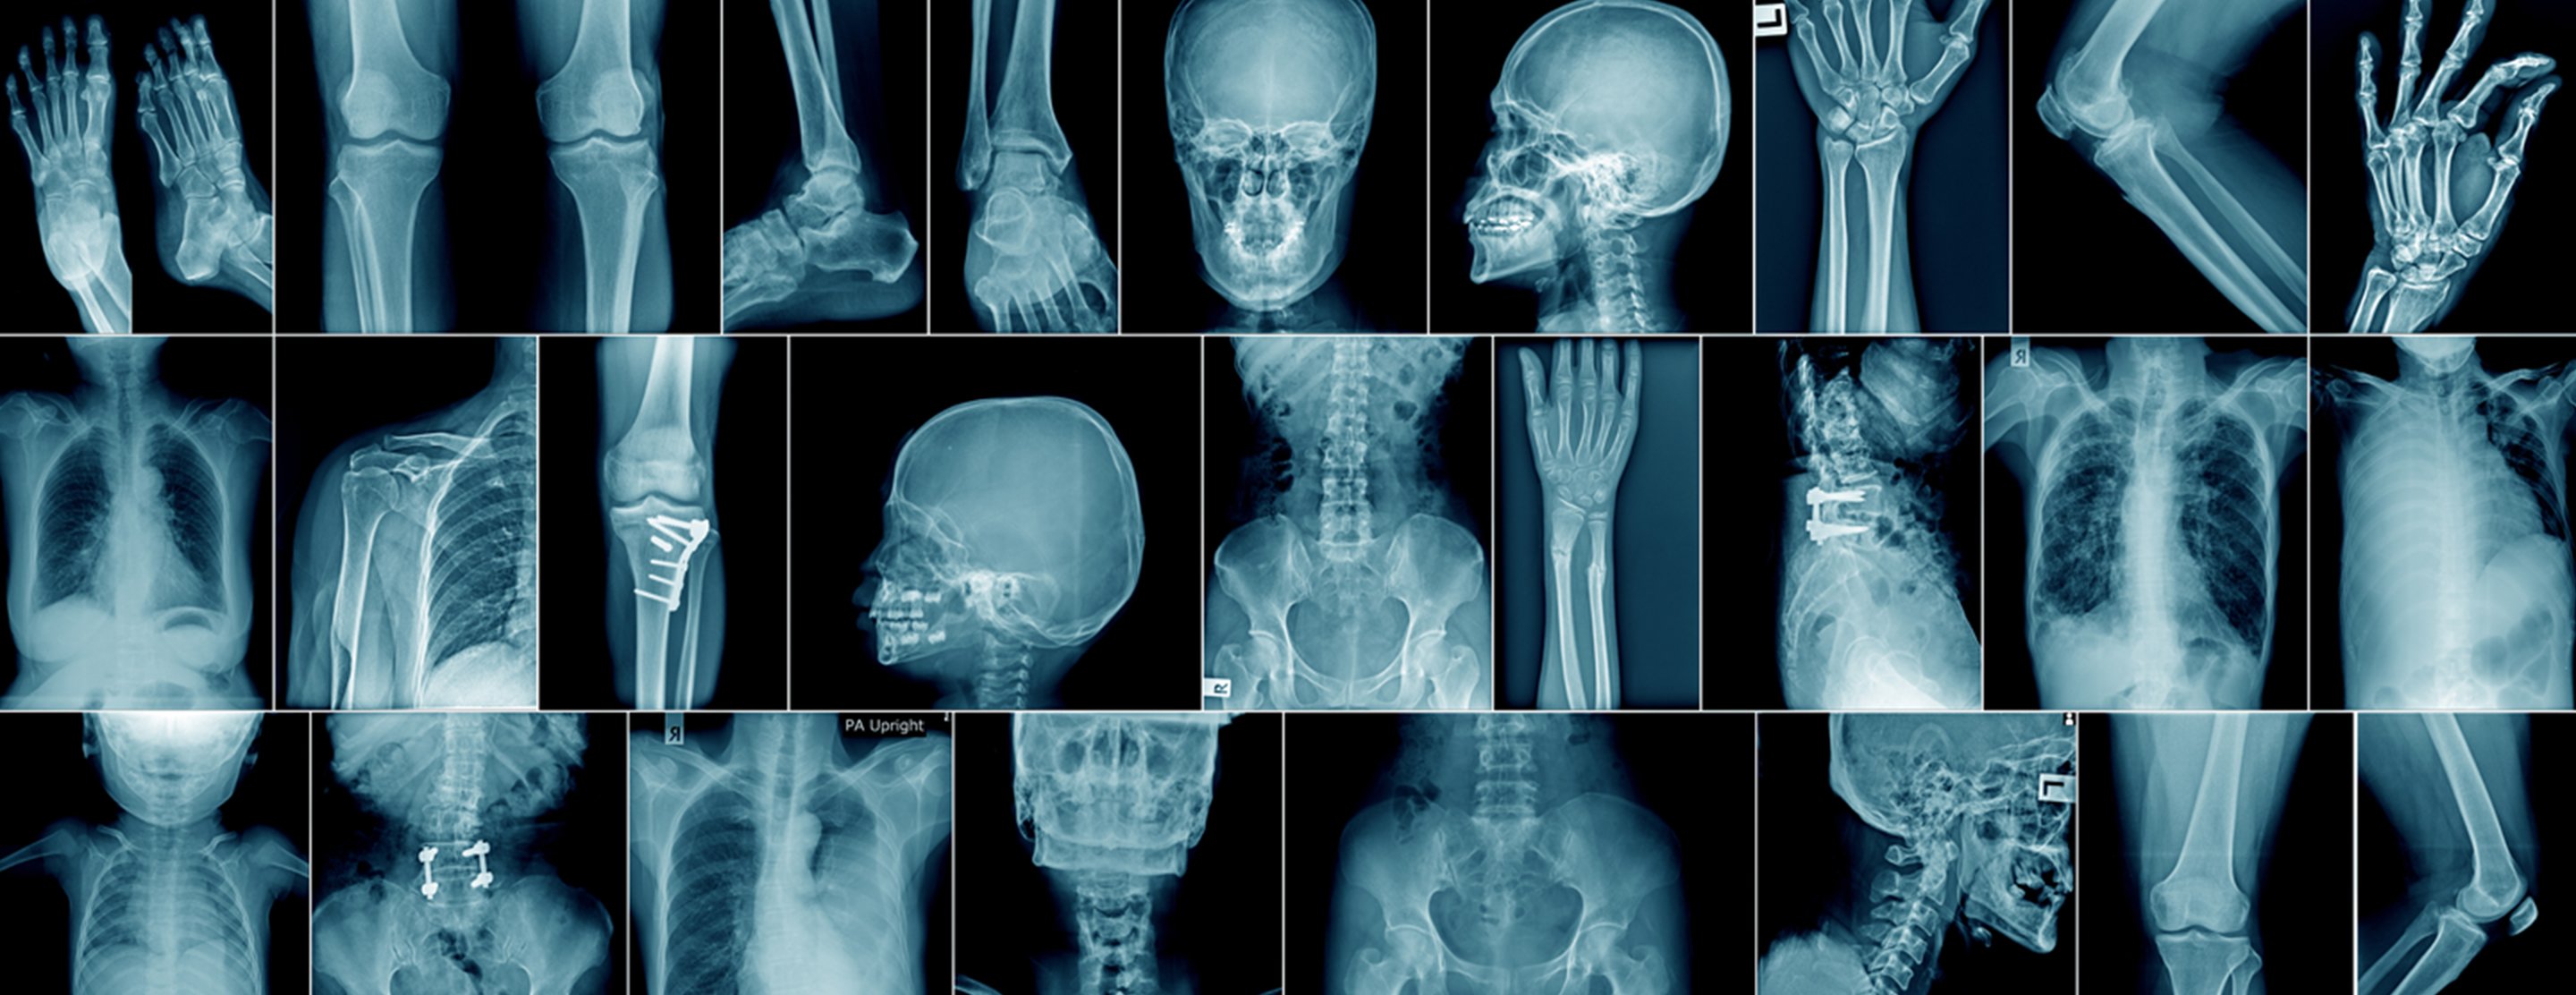

X-ray - skeleton

Definition

A skeletal

The x-rays pass through your body. A computer or special film records the images.

Structures that are dense (such as bone) will block most of the x-ray particles. These areas will appear white. Metal and contrast media (special dye used to highlight areas of the body) will also appear white. Structures containing air will be black. Muscle, fat, and fluid will appear as shades of gray.